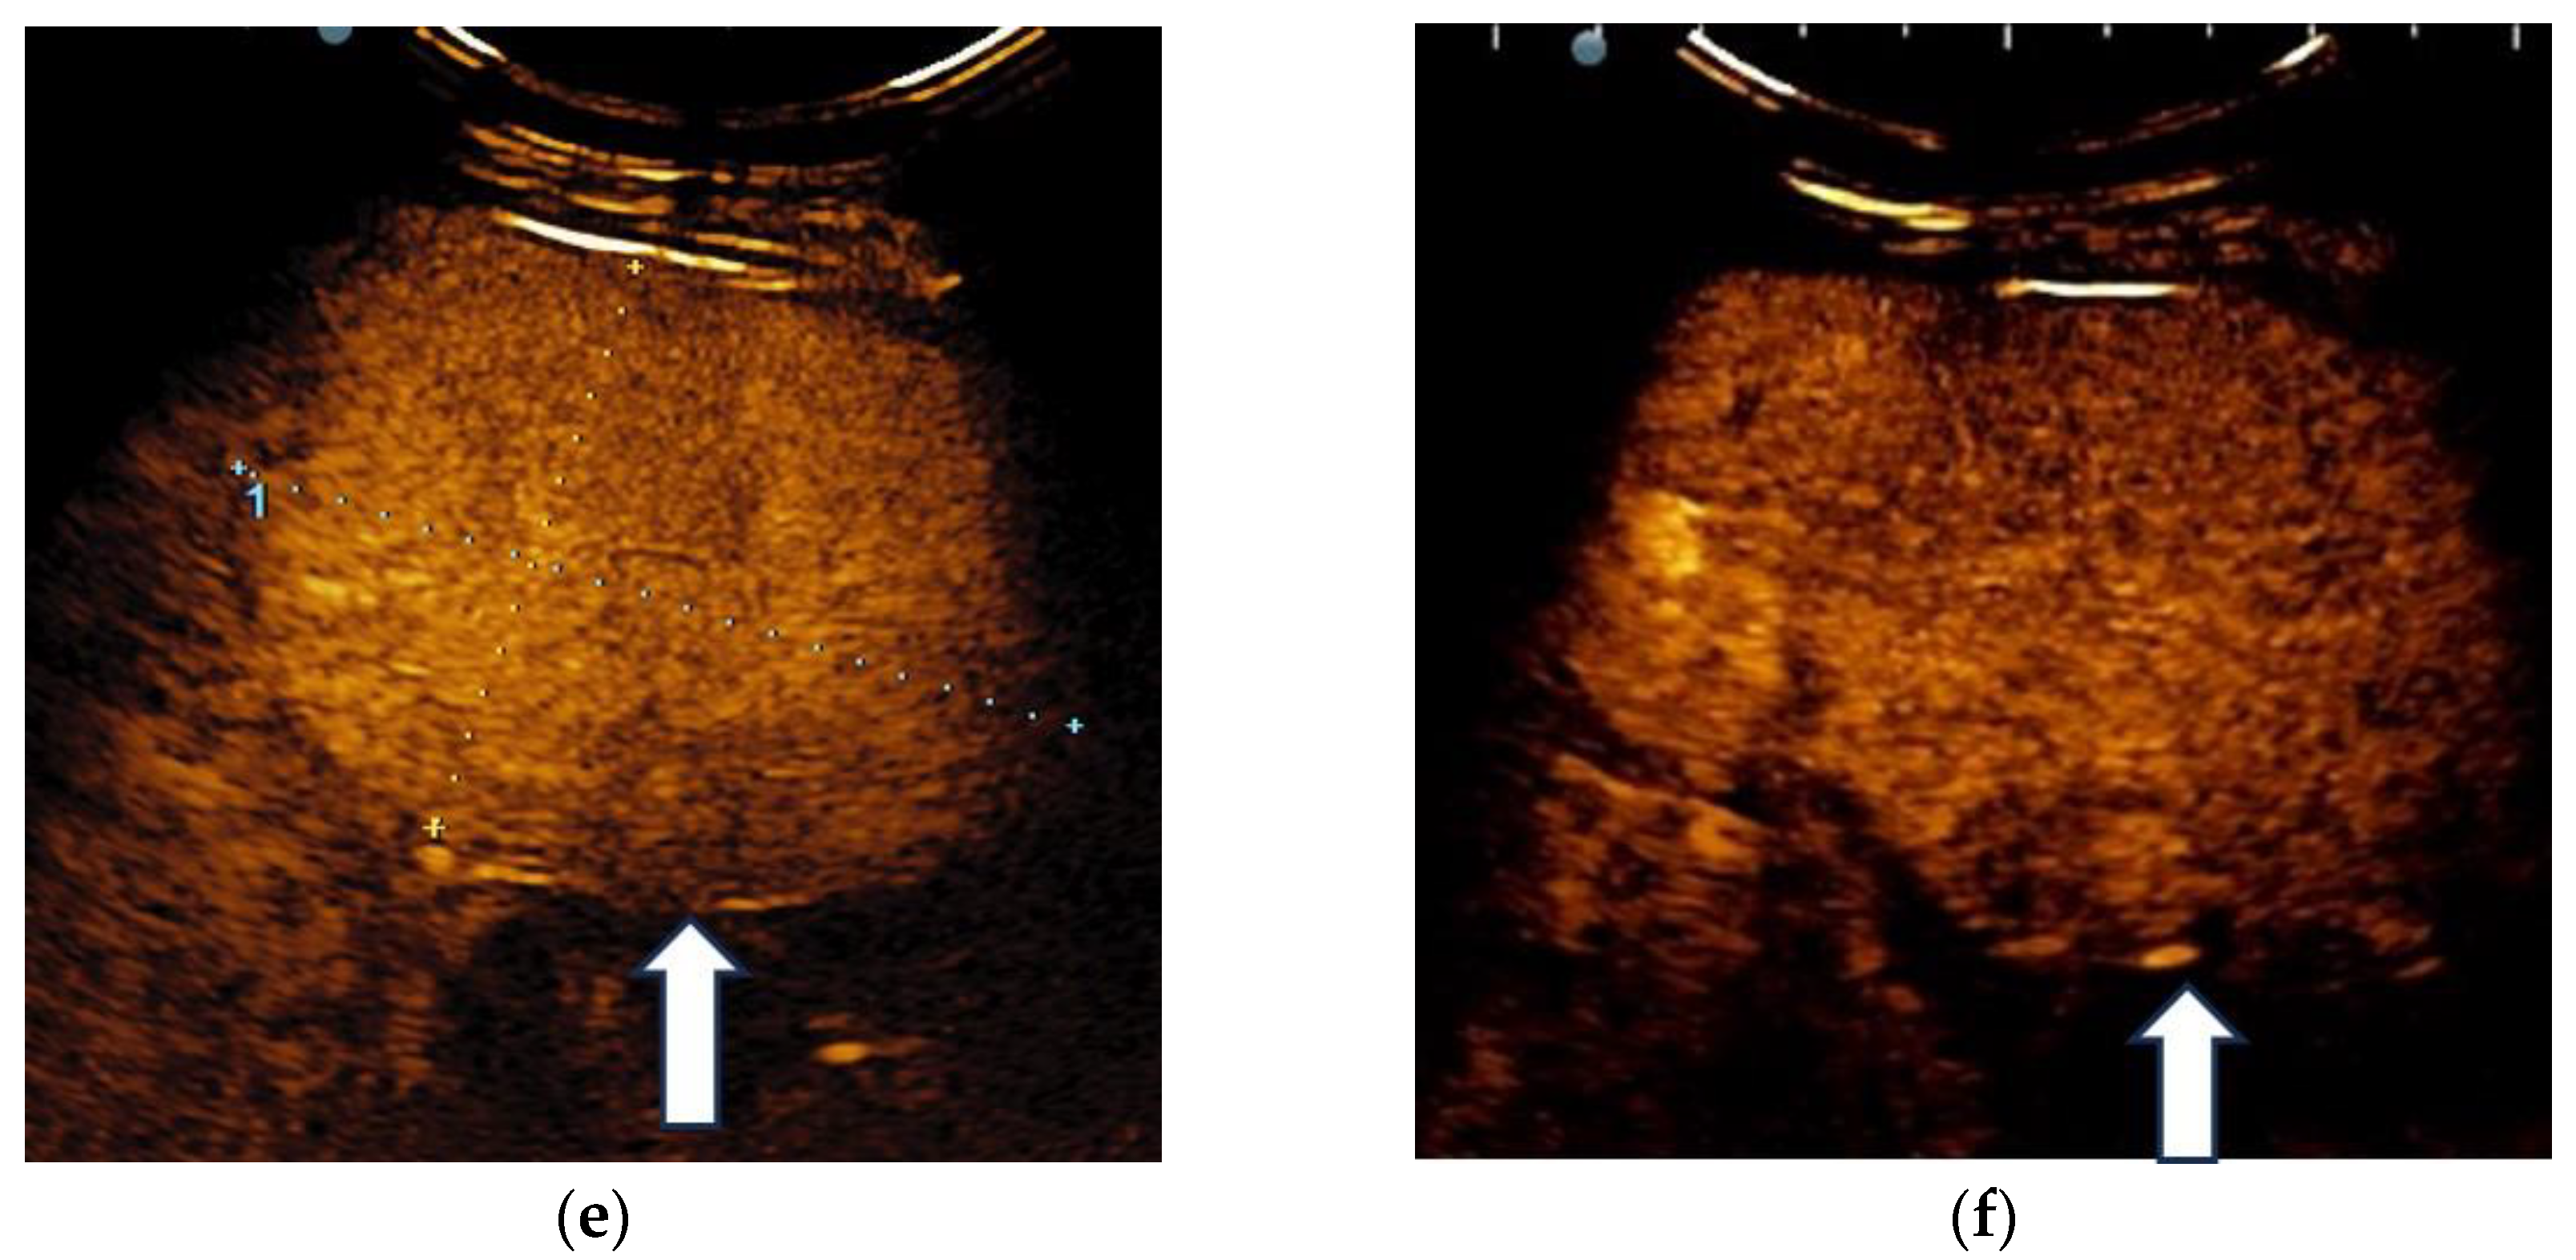

3.2. Contrast-Enhanced Ultrasound

3.3. Shear Wave Measurements in Liver Tumors